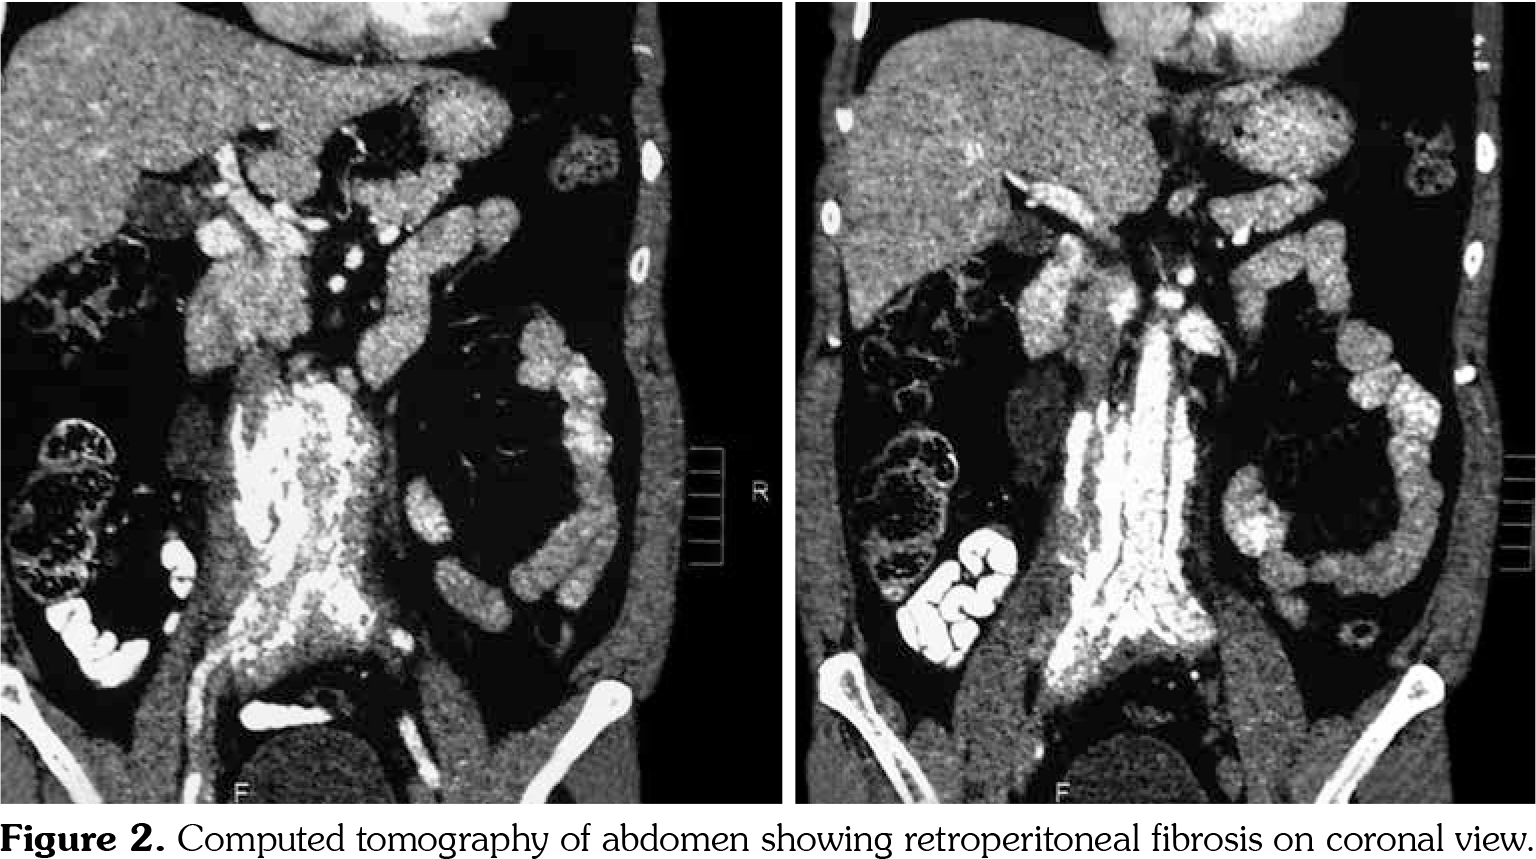

On investigations, his complete blood count was normal. Erythrocyte sedimentation rate was 88 mm in first hour. Random blood sugar was 93 mg/dL. His serum urea was 26 mg/dL and serum creatinine was 1.1 mg/dL. Liver function tests were within normal limits. Chest X-ray revealed non-homogenous opacities in bilateral lung fields. Pulmonary function tests revealed forced expiratory volume in one second (FEV1) of 61% and forced vital capacity (FVC) of 73%. FEV1/FVC ratio was 84%. Two-dimensional echocardiography was within normal limits. Ultrasonography of the abdomen revealed small-sized right kidney (6.9x2.9 cm) with dilated pelvi-calyceal system and dilated proximal ureter. Computed tomography (CT) of the abdomen revealed medial deviation of right ureter and presence of retroperitoneal soft tissue along infra-renal aorta and peri-caval area with calcification extending up to iliac vessels suggestive of RPF (Figures 1, 2, 3, and 4). High-resolution CT of the chest confirmed presence of interstitial lung disease (ILD). ANA profile (ENA) revealed that anti-U1 snRNP was strongly positive. Rest of the autoantibodies were negative. His serum immunoglobulin G levels were within normal limits. Thus, we arrived at a diagnosis of MCTD with RPF and ILD. He was started on mycophenolate 720 mg twice daily, hydroxychloroquine 200 mg once daily and deflazacort 6 mg once daily for MCTD, pirfenidone 400 mg twice daily for ILD and tamoxifen 20 mg once daily for RPF. On follow-up at six months, he was doing physically well. His symptoms of cough were reduced and dyspnea improved from NYHA class IV to class II. Repeat pulmonary function tests revealed FEV1 of 59%, FVC of 71% and FEV1/FVC ratio of 84%. However, repeat ultrasonography of the abdomen did not reveal any significant change in pelvi- calyceal system.

In 1972, Sharp et al.,[1] recorded a group of patients who had clinical features of SLE, SSc and PM with high titers of anti-extractable nuclear antigen antibody. They published it as a new disease entity: MCTD. Since then, there has been an increasing number of classification criteria published for the diagnosis of MCTD, namely, Kasukawa et al.[3] Alarcon-Segovia and Villareal[4] and Kahn and Appelboom.[5] There has been no consensus on clinical features owing to varied manifestations and frequent overlap of symptoms with other autoimmune conditions. However, high titers of antibodies against U1 snRNP have been found in most patients.[6] Our patient had symptoms of dysphagia, epistaxis and ocular sicca coupled with high titers of anti-U1 snRNP which led us to the diagnosis of MCTD. He also had pulmonary involvement in the form of ILD. One study showed 47% of cases of MCTD to have ILD.[7] The most frequent histological picture seen is non-specific interstitial pneumonia, followed by usual interstitial pneumonia and lymphocytic interstitial pneumonia.[8] RPF was first reported by Ormond[9] in 1948. It is a rare condition characterized by inflammation and fibrosis of the retroperitoneum, around the infra-renal portion of abdominal aorta and iliac arteries and usually entraps ureters and inferior vena cava.[10] A recent study reported incidence of RPF around 1.3 per 100,000 population per year in Netherlands.[11] The mean age of presentation is around 50 years with male predominance (2:1-3:1). Abdominal CT and magnetic resonance imaging are the investigations of choice for the diagnosis of RPF and they reveal a homogenous mass near the lower abdominal aorta and iliac arteries that surround and displace the ureters medially. Medical therapies for RPF include steroids, tamoxifen, other immunosuppresives such as azathioprine, mycophenolate and anti-CD20 antibody such as rituximab. In one single-center prospective observational study of 55 patients with RPF treated with tamoxifen monotherapy for a minimum of two years, 47 (85%) patients reported substantial resolution of symptoms after a median treatment duration of three weeks. There was a mass regression in 39 (71%) patients at four months and 47 (85%) patients at eight months of follow-up, respectively. Recurrence- free survival in patients with treatment success after post-treatment follow-up of 21 months was 68%.[12] To our knowledge, there is no previously published case report on presence of RPF in a patient of MCTD. This is indeed a rare occurrence.